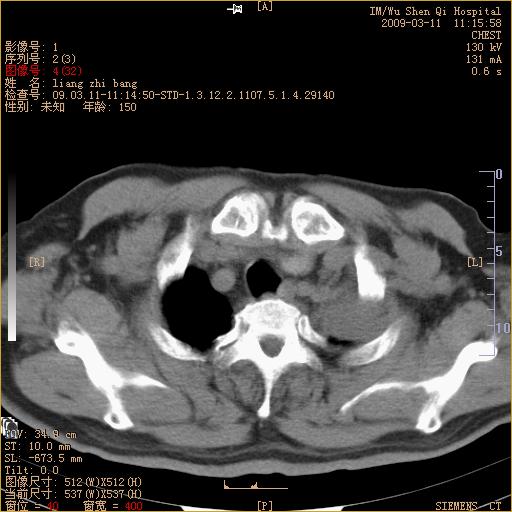

标题: CT18604:男,60岁,咳嗽一月余 [打印本页]

标题: CT18604:男,60岁,咳嗽一月余

1)考虑左肺上叶中央型肺癌并左肺上叶肺不张;建议必要时行纤支镜检查进一步明确诊断。2)左侧胸腔积液。

肺门肿块、支气管开口闭塞伴肺不张及胸水!典型的中心型肺癌变现!

1、左肺上叶中央型肺癌并上叶阻塞性肺不张。

左肺们肿块并左肺上叶不张。考虑左肺中心性肺癌并左肺上叶不张及左侧胸腔积液